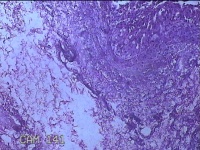

右卵巢黄体囊肿

性别

女

年龄

41岁

临床诊断

右卵巢黄体囊肿破裂

一般病史

下腹痛3小时。

标本名称

大体所见

灰白暗红色囊性肿物2x0.8x0.7cm一个,表面糜烂,切开肿物,内见大量凝血块,囊壁厚约0.1cm。